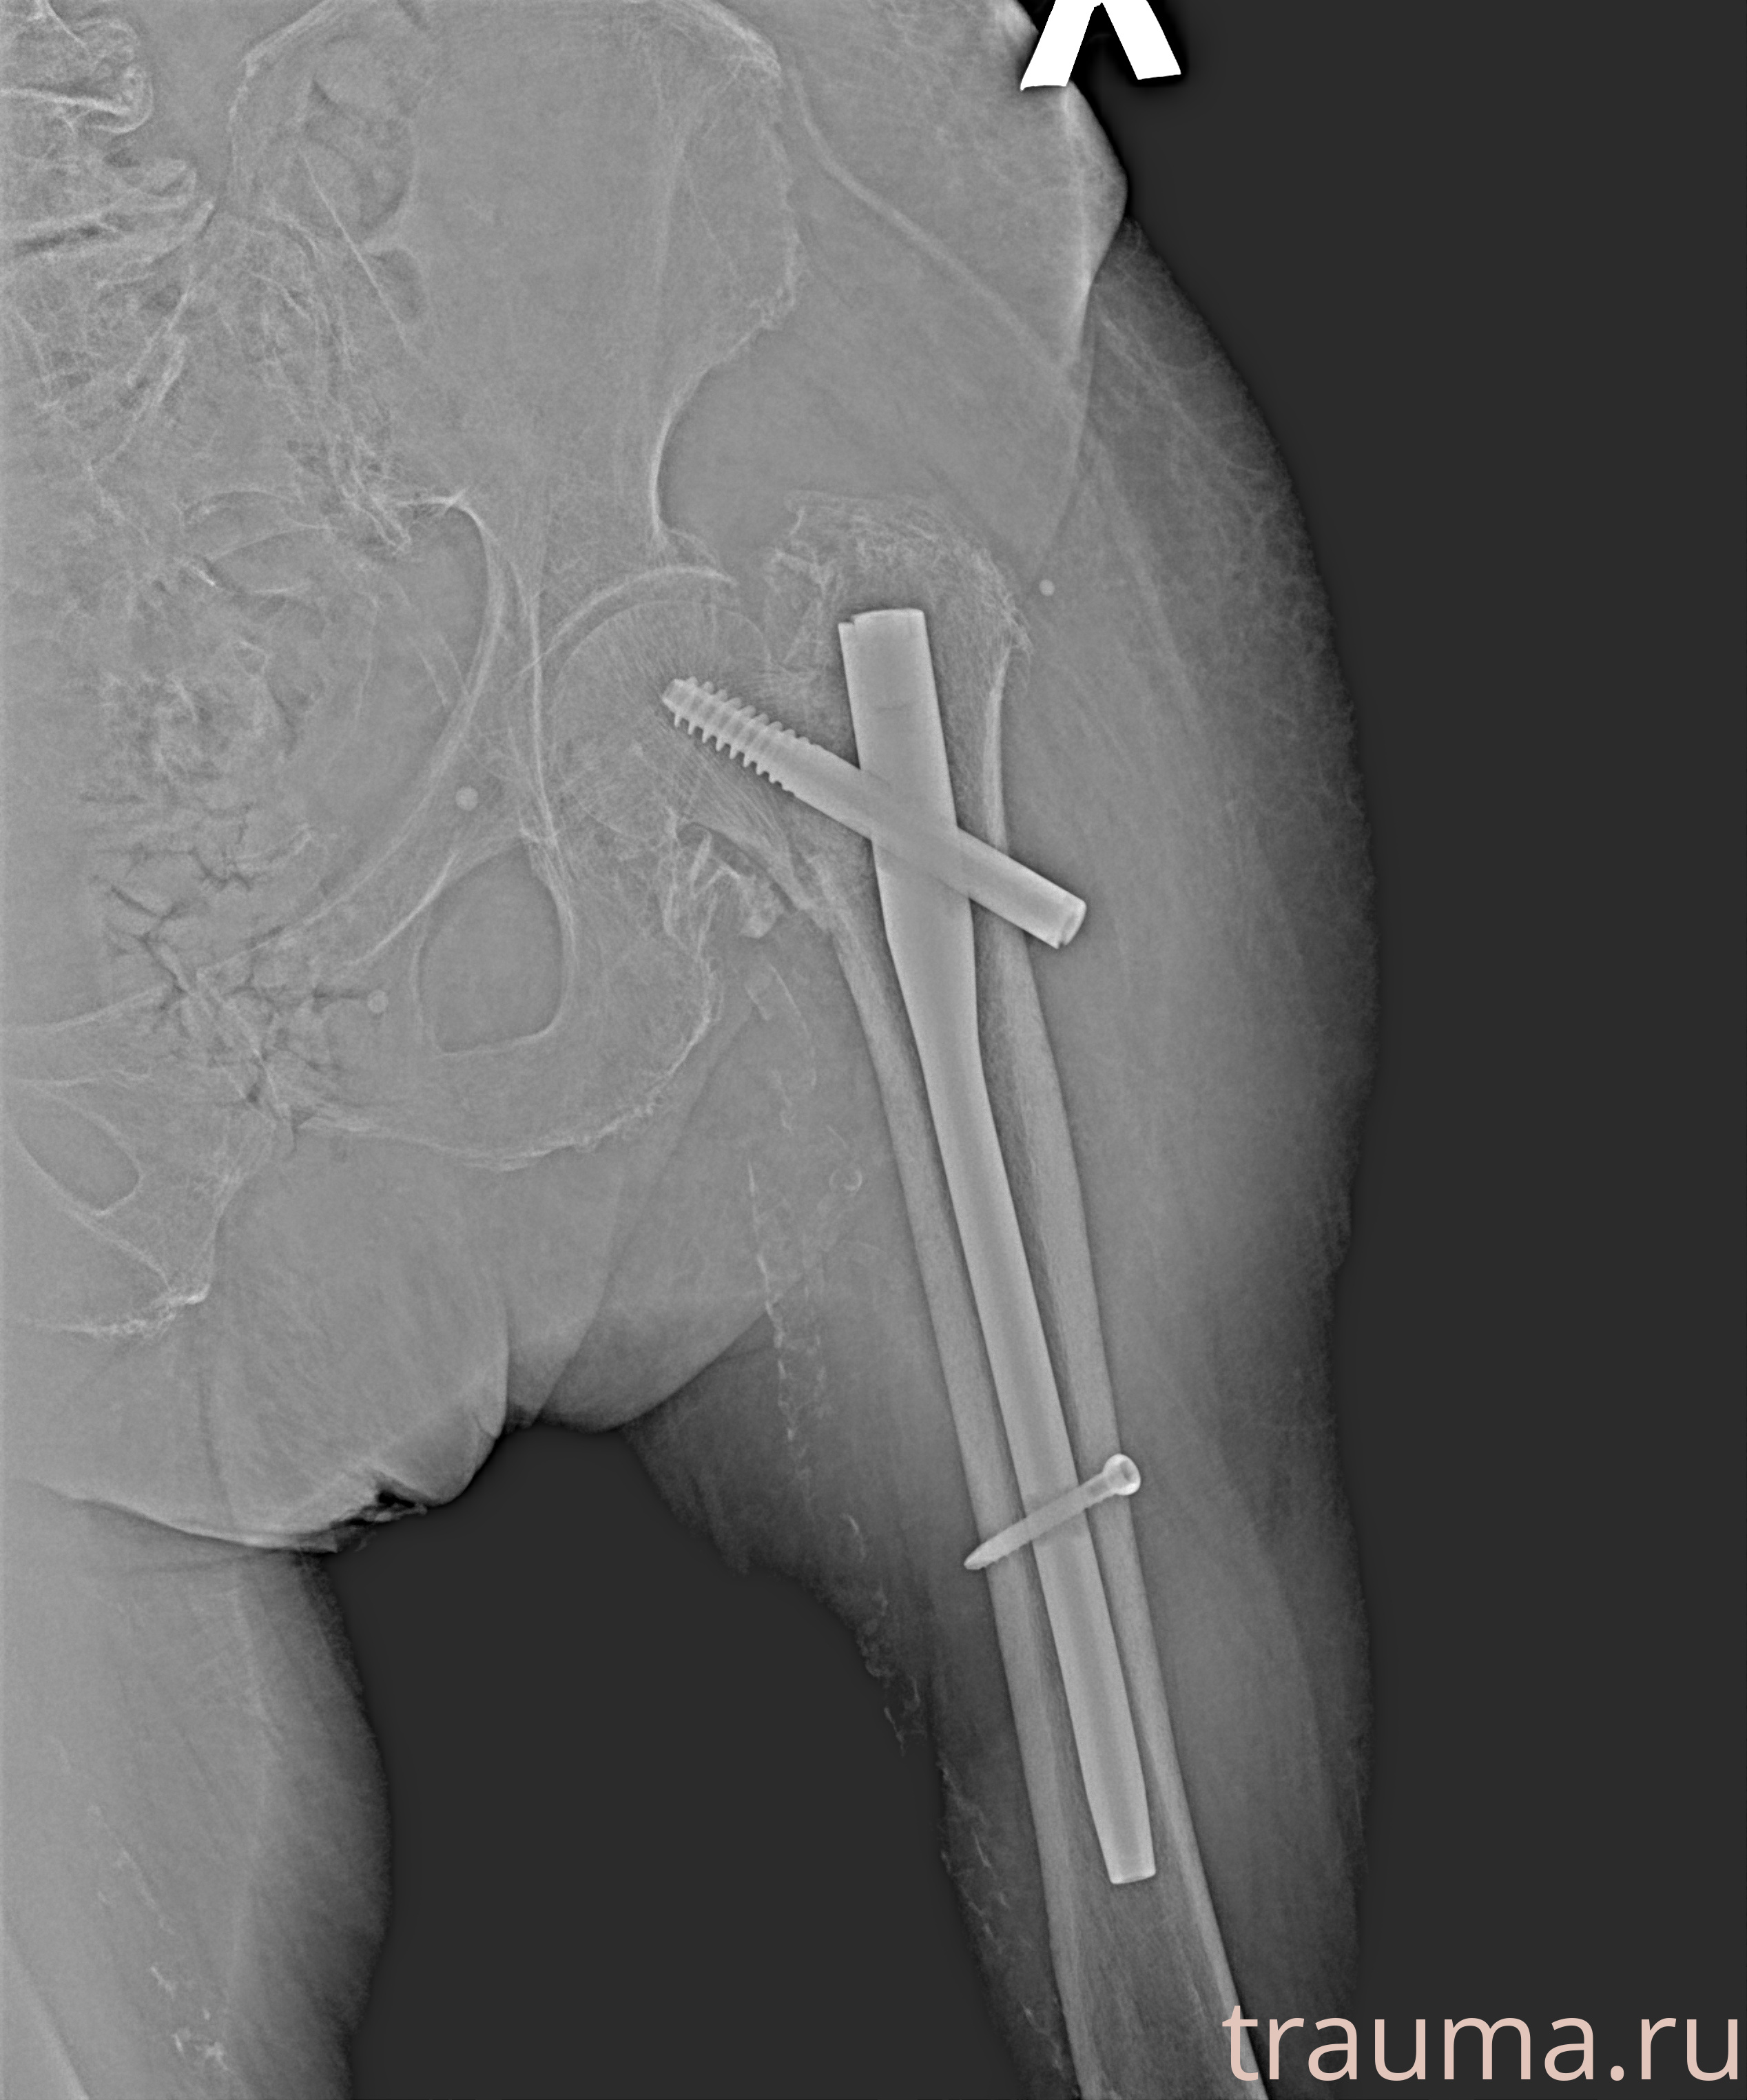

Рентгенограммы